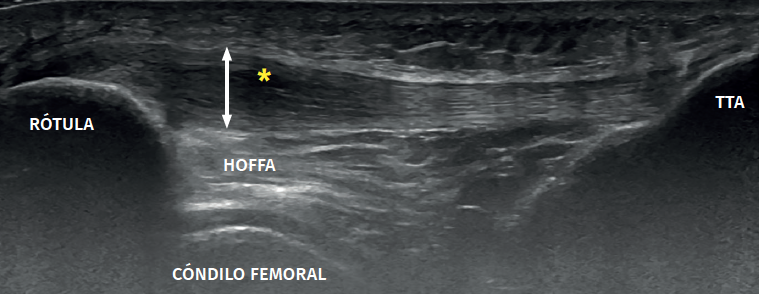

Figure 3. Ultrasound view of proximal patellar tendinopathy with linear probe in craniocaudal longitudinal panoramic view (from left to right). Note the area of decreased echogenicity (hypoechoic), marked with an asterisk, loss of the fibrillar pattern in the deepest and proximal region of the tendon secondary to disruption of the collagen bands, and anteroposterior 8.5 mm thickening (double arrow). ATT: anterior tibial tuberosity.

The ultrasound study of a damaged tendon evidences hypoechogenicity and loss of the fibrillar pattern, the appearance of disorganised connective tissue, and thickening of the tendon (Figure 3). In some cases we observe well delimited hypoechoic images indicating intra-substance rupture with nodular or fibrillar shapes, commonly manifesting in the deepest zone of the tendon in the lower pole adjacent to the patella (Figure 4).

It is also common to identify cortical irregularities in the proximal enthesis of the tendon at the point where it joins the patella, involvement of the paratendon and adherences to Hoffa's fat pad. Any calcifications will be seen as white hyperechogenic zones (Figure 5).